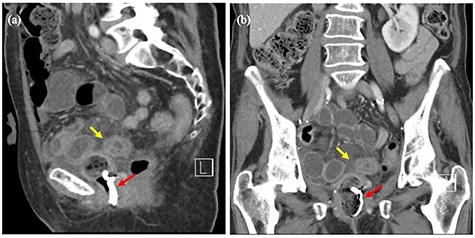

Computed tomography scan of the abdomen revealed small volume of free fluid and inflammatory fat stranding in the pelvis with loops of thick-walled distal small bowel. Packing material was seen in the vaginal vault (Fig. 2a and b).

(a and b) Computed tomography images of the pelvis before surgery. Red arrows showing packing material in the vaginal vault. Yellow arrows showing loops of thick-walled distal small bowel.